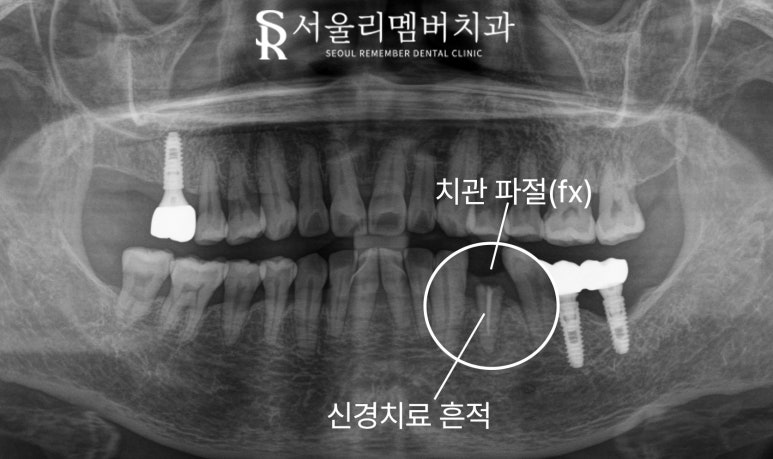

오늘 보라매 치과 에서 보여드리는 케이스도

파노라마 엑스레이 상에서

내부에 하얀 재료가 채워져있는 것을 보아

과거에 신경치료를 받았던

왼쪽 아래 첫 번째 작은 어금니에

문제가 생긴 것으로 관찰되며,

자세히 보면 치아의 머리 부분인

치관이 파절되었습니다.